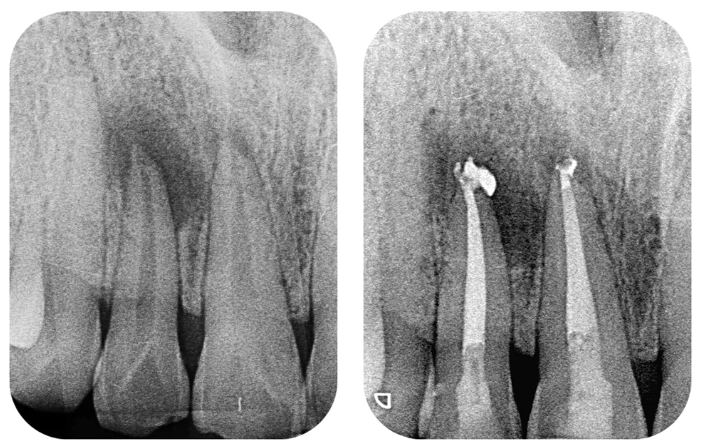

- More Roots and Canals: Front teeth might have one root. A molar can have two, three, or even four roots, each with one or more canals. Finding and cleaning all of them is a precise task.

- Complex Anatomy: The canals inside molar roots can be curved, narrow, or branch out in unexpected ways. It's like cleaning a intricate, microscopic cave system.

Step 2: The Work Begins – Access and Cleaning

Once you're numb, the dentist places a rubber dam around the tooth. It's a small sheet of latex or non-latex material that isolates the tooth, keeping it clean, dry, and preventing you from swallowing any tiny instruments. Then, they drill a small opening in the top (crown) of your tooth to access the pulp chamber.

Using very fine instruments called files, they carefully remove the infected pulp tissue from each canal. This is the "cleaning" phase. They'll also flush the canals with antibacterial solutions (like sodium hypochlorite—basically a mild bleach solution) to disinfect and flush out debris. This part can take time, especially for a multi-rooted molar.

Step 3: Filling and Sealing the Canals

After the canals are cleaned, shaped, and dried, they need to be filled to prevent re-infection. A biocompatible material, usually a rubber-like substance called gutta-percha, is used to fill the space. It's sealed in place with a dental adhesive cement. The goal is to hermetically seal the root canal system.

- Missed Canals: Remember those complex molar anatomy? Sometimes a tiny, extra canal is missed during cleaning and remains infected.

- Incomplete Cleaning: Severely curved or blocked canals might not be fully cleaned.

- Poor Seal: If the filling material doesn't seal the tip of the root perfectly, bacteria can leak back in.

Signs of a failing root canal are similar to the original problem: pain, swelling, a recurring pimple on the gum (sinus tract), or sometimes it's only visible on a follow-up X-ray.

If a root canal fails, you have options. An endodontic re-treatment is the first line. This means reopening the tooth, removing the old filling material, finding and cleaning the missed area, and re-filling. It's more complex but can often save the tooth. Another option is an apicoectomy, a minor surgical procedure where the tip of the root is accessed through the gum and bone, the infected tip is removed, and a filling is placed to seal the end. In some cases, if the tooth is not salvageable, extraction becomes necessary.